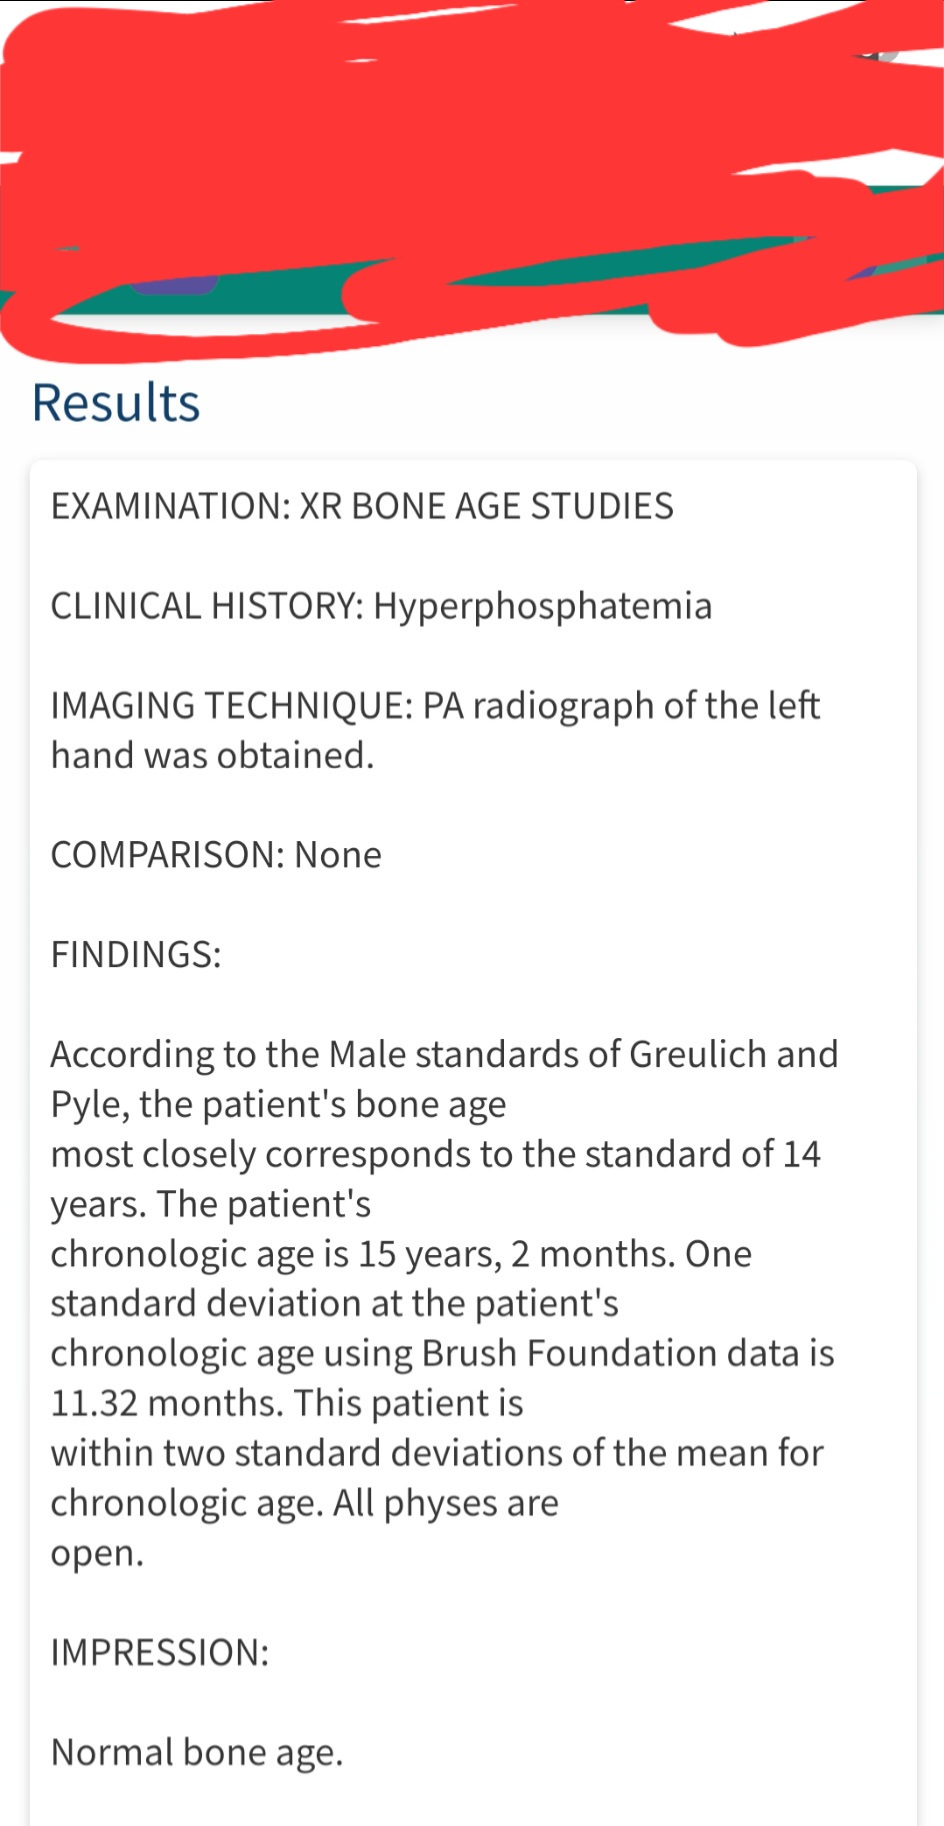

Age now 15 4 months

xrays and the examination done on October 17

Height 6'0

xrays and the examination done on October 17